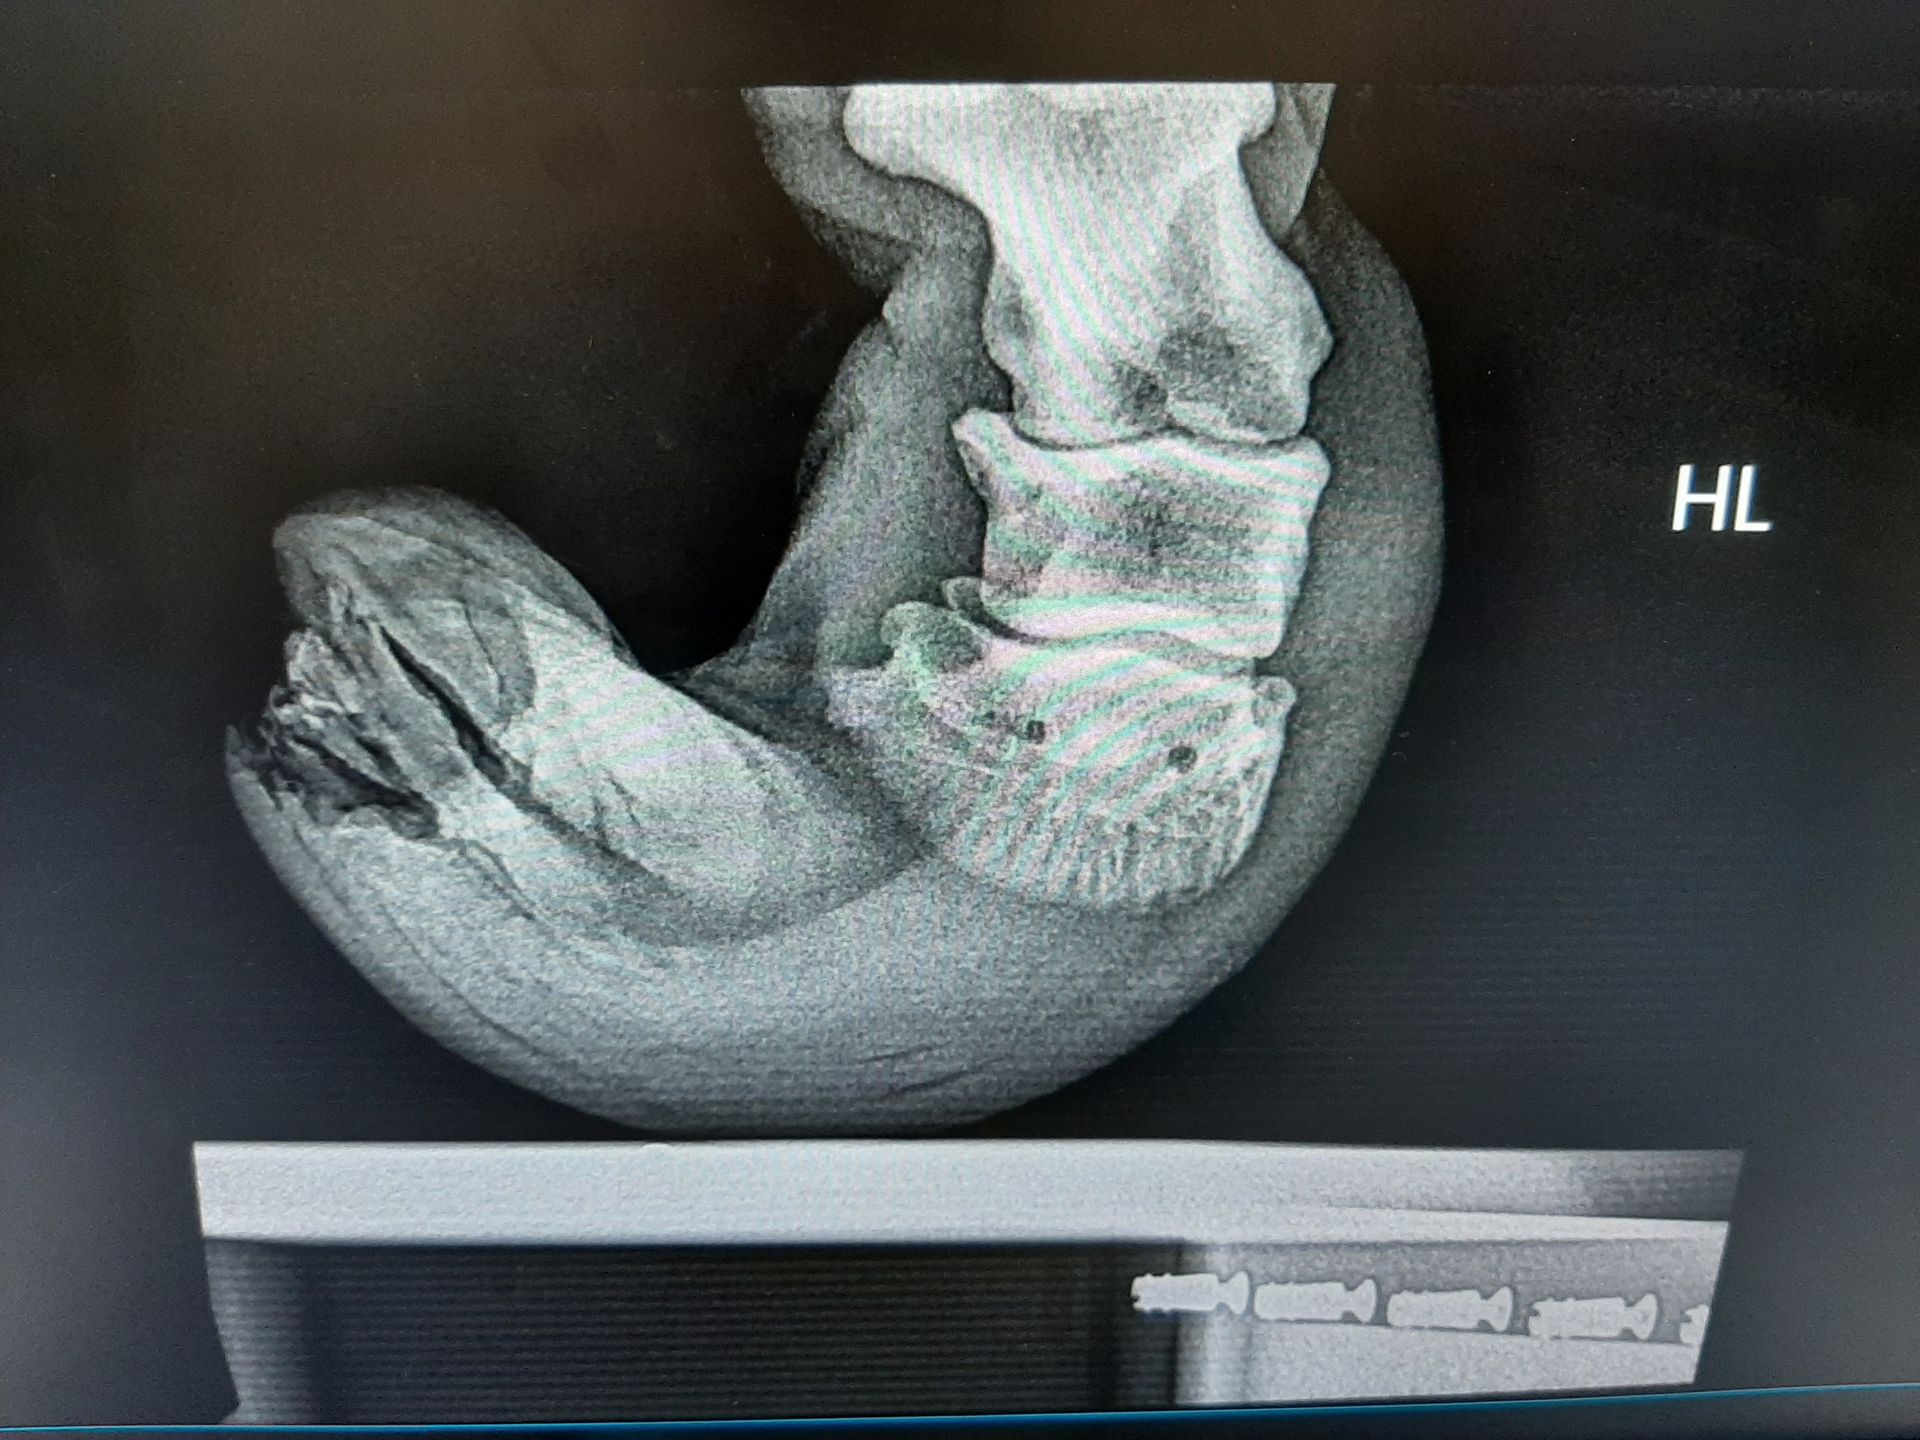

Fallbeispiel

Pferd mit Hukrebs

Behandlung: Entfernen des betroffenen Gewebes

Auf den Bildern sieht man, wie das Pferd unter Vollnarkose auf dem OP-Tisch liegt. Ich habe erst die Hufe ordentlich sauber gemacht. Die Hufe wurden desinfiziert und das gesamte betroffene Gewebe entfernt. Nach einige Tagen mit Verband hat das Pferd ein Deckeleisen bekommen.